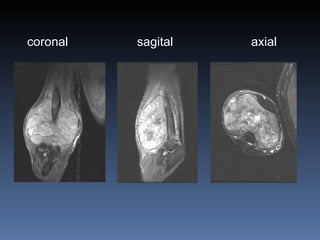

Paciente se coloca en un campo magnetico potente Imagen multiplanar Excelente contraste de tejidos blandos Imagen por resonancia magnetica (IRM)

coronal   sagital axial

Desventajas Contraindicaciones Cuerpos extranos metalicos en orbita Marcapasos  Aparatos neuroestimuladores  Claustrofobia Riesgo teórico en el primer trimestre de gestación Artefactos por objetos ferromagneticos Imagen de anatomia osea, fracturas y descalcificacion Imagen por Resonancia Magnetica (IRM)